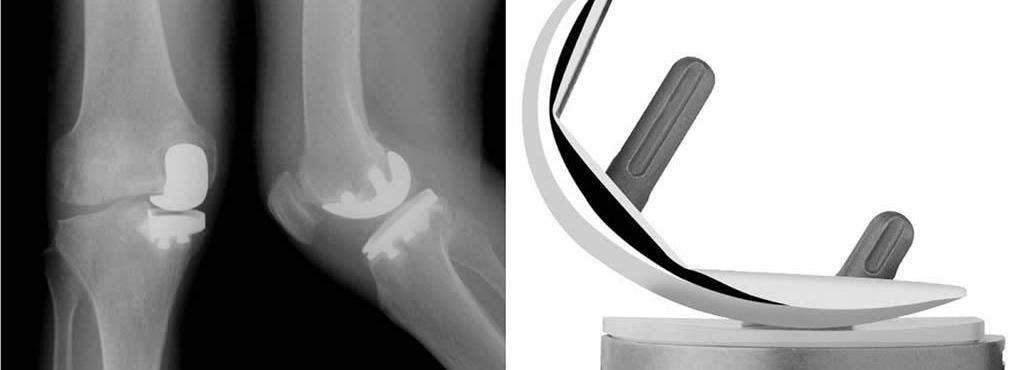

Proteza de genunchi unicompartimentală: indicații, avantaje și experiența chirurgului

Proteza de genunchi unicompartimentală reprezintă o soluție modernă și minim invazivă pentru pacienții care suferă de afectarea limitată a articulației genunchiului. Această intervenție este utilizată [...]